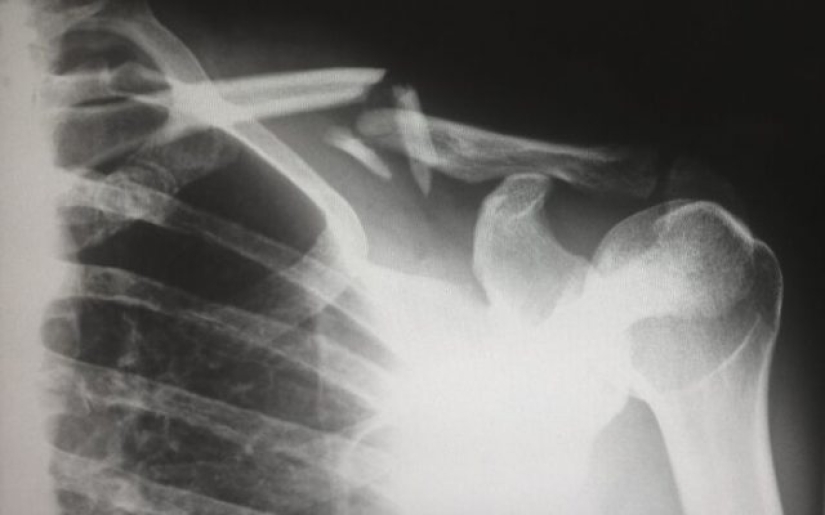

1. When x-ray technology first became widely available to pediatricians, they noticed an astounding number of broken bones. Puzzled doctors have suggested that this is the first time a previously unknown bone disease is being observed in children. It turns out we had no idea how common child abuse was.